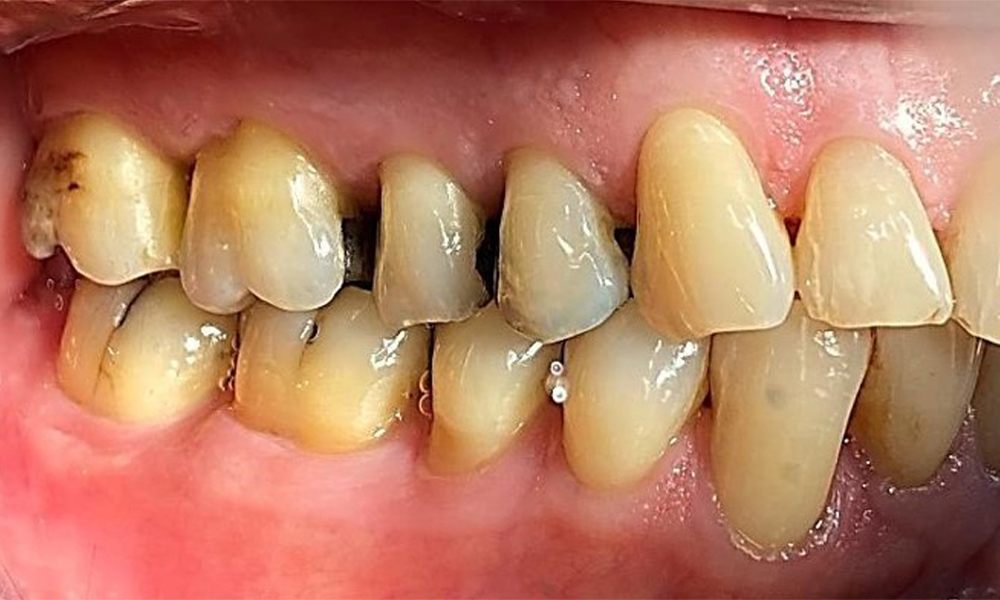

Pacientul prezintă dentiție completă cu 28 de dinți, care include obturații din amalgam și compozit pe molari și premolari. Există un spațiu marginal clinic vizibil la 14. Molarul 27 prezintă un inlay din aur adecvat. Se observă, de asemenea, atriții și abrazii generalizate. (Fig. 2, Fig. 3, Fig. 4, Fig. 5, Fig. 6)

Pacientul prezintă boală parodontală în stadiul II, gradul B (5). Profunzimile clinice de sondare observate, între 1 și 3 mm, se încadrează în limitele fiziologice. Localizat, s-au observat profunzimi de 5 mm, la nivel meziopalatin, atât pe 17, cât și pe 27. Se constată recesiuni generalizate de 1-3 mm, cu pierderi parțiale ale papilelor interdentare (Fig. 2, Fig. 3, Fig. 4)